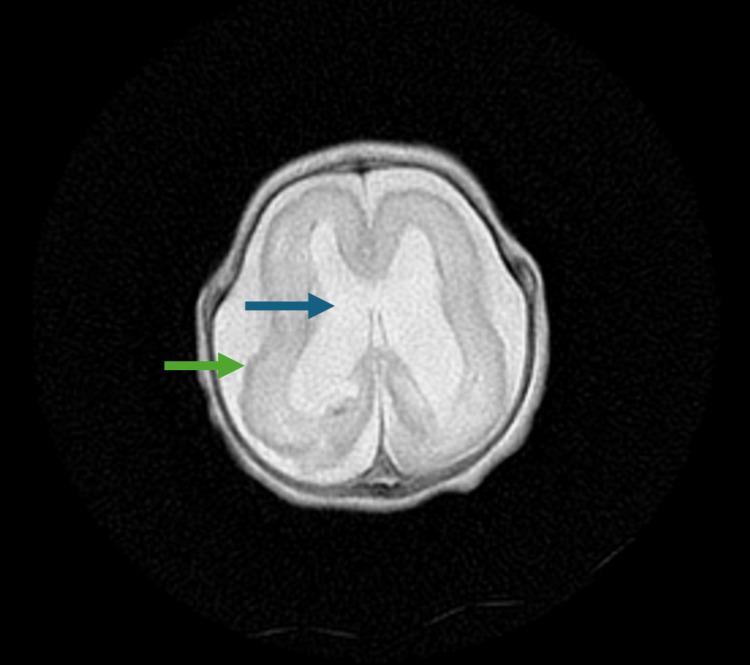

This case report investigates the management of a 24-week-old neonate with congenital cytomegalovirus (CMV) infection and its sequelae, including severe intrauterine growth restriction, thrombocytopenia, and brain anomalies, ultimately progressing to lissencephaly. The diagnostic challenges included delayed clinical suspicion of congenital CMV, which was not identified until after delivery through CMV DNA polymerase chain reaction, and differentiating its symptoms from other potential causes of the neonate's condition. Aggressive interventions included antibiotics, antiviral therapy with ganciclovir, and supportive measures such as intubation, CPR, respiratory support, blood transfusions, and management of coagulopathy. Despite these efforts, the patient deteriorated due to progressive hypoperfusion, hypoxemic cardiorespiratory failure, and disseminated intravascular coagulopathy. Due to the poor prognosis and extent of multiorgan damage, support was withdrawn per parental consent. This case highlights the complications encountered when managing an advanced-stage neonatal CMV infection and emphasizes the importance of a multidisciplinary and holistic approach to guide diagnosis and treatment.

本病例报告探讨了一名24周大先天性巨细胞病毒(CMV)感染新生儿及其后遗症的治疗情况,这些后遗症包括严重的宫内生长受限、血小板减少症和脑异常,最终发展为无脑回畸形。诊断面临的挑战包括先天性CMV的临床怀疑延迟,直到分娩后通过CMV DNA聚合酶链反应才得以确诊,以及将其症状与新生儿病情的其他潜在病因相区分。积极的干预措施包括使用抗生素、更昔洛韦抗病毒治疗,以及诸如插管、心肺复苏、呼吸支持、输血和凝血病管理等支持措施。尽管采取了这些措施,患者仍因进行性低灌注、低氧性心肺衰竭和弥散性血管内凝血而病情恶化。由于预后不良和多器官损伤程度严重,经家长同意停止了支持治疗。本病例突出了晚期新生儿CMV感染治疗中遇到的并发症,并强调了多学科整体方法在指导诊断和治疗方面的重要性。